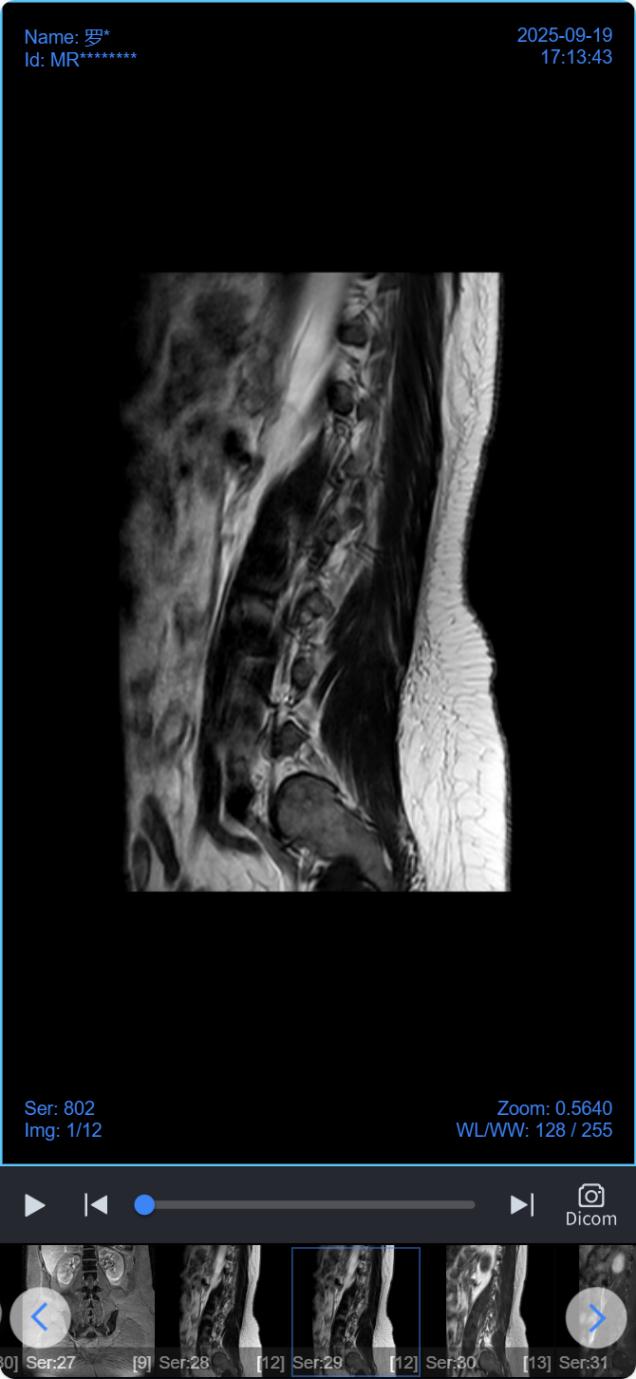

点击“报告单”和“查看影像”分别查看检查报告单及检查电子影像;